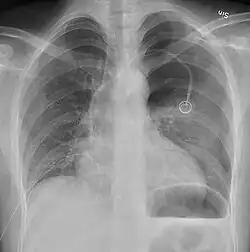

Una radiografía realizada en proyección postero-anterior (de atrás hacia delante) y durante la inspiración máxima constituye la forma de diagnóstico más frecuente.[38] Las imágenes realizadas en espiración, al contrario, no poseen valor diagnóstico significativo,[20] aunque pueden resultar útiles cuando existe una alta sospecha de neumotórax, pero la radiografía en inspiración aparece normal.[39] Si este es el caso, también pueden realizarse radiografías de proyección lateral, aunque esta práctica no se realiza con frecuencia.[20][31]

-

radiografía anteroposterior que muestra un neumotórax de reducido tamaño en el pulmón izquierdo, causado por una punción -

Radiografía lateral en inspiración, que muestra el neumotórax en la parte posterior -

Radiografía anteroposterior en espiración en la que también puede observarse el neumotórax

A veces puede darse una desviación del mediastino hacia el lado contrario en el que se halla el neumotórax debido a las diferencias de presión que crea esta patología. La presencia de esta desviación no implica la existencia de un neumotórax a tensión, que habitualmente se diagnostica a través de signos de gravedad como hipoxia severa y choque obstructivo.[30]

El tamaño del neumotórax (es decir, la cantidad que este ocupa en la cavidad pleural) puede determinarse midiendo la distancia entre la caja torácica y el borde del pulmón. Esto es de relevancia para el tratamiento, ya que los neumotórax de menor tamaño a menudo poseen un enfoque terapéutico distinto. Una distancia de dos centímetros significa que el neumotórax ocupa un 50 % del hemitórax.[20] Las guías de práctica clínica afirman que esta medida debe darse a partir del hilio pulmonar, con un umbral de referencia de dos centímetros para indicar la presencia de un neumotórax de menor o mayor tamaño. La medida también puede realizarse a partir del ápice pulmonar, y en este caso el umbral es de tres centímetros,[40] aunque esta forma de medición puede hacer pensar que el tamaño del neumotórax es mayor si este se encuentra concentrado en la parte superior de la caja torácica.[20][31] Aun teniendo en cuenta esto, estos métodos de medida no poseen una correlación perfecta con el tamaño del neumotórax y, aunque el TAC ofrece imágenes más precisas en este sentido, se desaconseja su uso en estas situaciones clínicas.[20]

No todos los neumotórax son uniformes; algunos ocupan solamente un pequeño espacio en un espacio particular de la cavidad pleural.[20] A veces, pueden hallarse pequeñas cantidades de líquido en la radiografía (hidroneumotórax), que puede estar constituido por sangre (hemoneumotórax).[30] En algunos casos la única manifestación de estos que se da en la radiografía es el signo del surco profundo, por el cual se da un aumento del espacio entre la caja torácica y el diafragma por la presencia de líquido.[35]